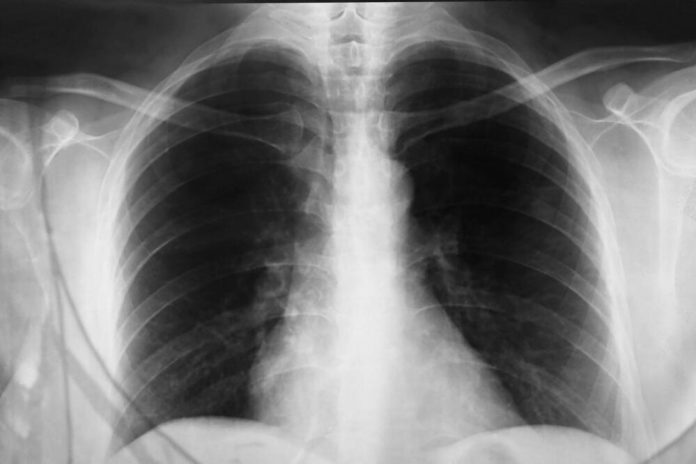

Lečenje upale pluća zavisi od uzročnika. Da bi se dijagnostikovala, lekar će uzeti istoriju bolesti, obaviti fizikalni pregled, kao i rendgen pluća kako bi se utvrdilo prisustvo zapaljenja. Ponekad su potrebni i laboratorijski testovi kako bi se identifikovao tačan uzročnik. Ako se utvrdi da je u pitanju bakterijska pneumonija, pacijentu će biti propisani antibiotici, dok se za virusnu infekciju obično prepisuju lekovi za snižavanje temperature i olakšavanje simptoma. U težim slučajevima, pacijenti će biti hospitalizovani, a može biti potrebna i terapija kiseonikom.